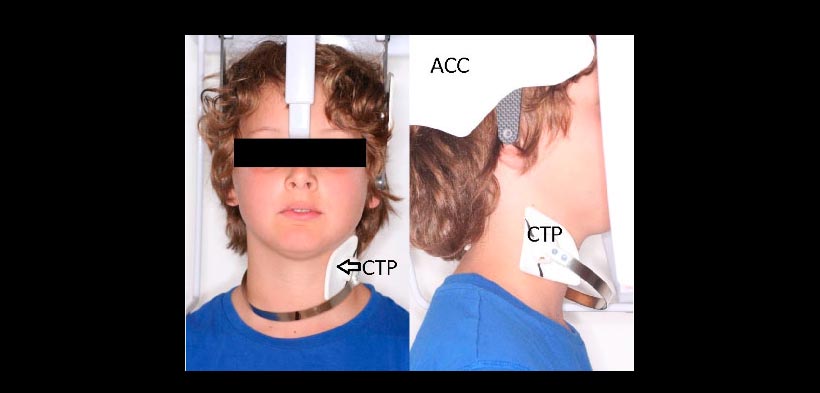

Recientemente, el colimador craneal anatómico (ACC) (ver figura 1), se introdujo para proteger la zona craneal y base del cráneo de la radiación. Esta zona craneal no tiene información de diagnóstico para el ortodoncista. Otra área que está en el campo de visión de las radiografías laterales sin información de diagnóstico es la región de la tiroides. La glándula tiroides es uno de los órganos más radiosensible en la región de la cabeza y el cuello. Las directrices europeas y norteamericanas indican que el uso e protectores tiroideos deben ser de carácter obligatorio para los niños y en los adultos siempre y cuando la zona de la tiroides no va a interferir con el examen.

Los protectores cefalométricos de tiroides (TCP) (ver figura 1), para proteger a la glándula tiroides durante la toma de una radiografía lateral se introdujeron por primera vez por Block en 1977 y están fácilmente disponibles. Sin embargo algunos exámenes hechos en la radiografía lateral utilizan las vértebras como indicadores de madurez esquelética (SMI), por lo cual es necesario que estos protectores protejan a la tiroides pero sin oscurecer la zona cervical.

Figura 1. Utilización del colimador craneal anatómico (ACC) y del protector tiroideo cefalométrico (CTP) antes de la exposición de una radiografía lateral.